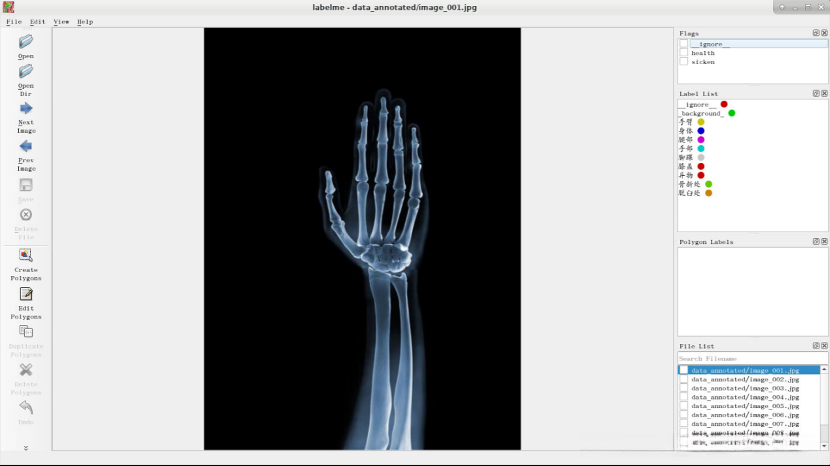

出现如图所示页面

观察图像,判断患者是否健康,认为该患者是健康的,所以flag选择“health”。

请在电子图像中识别出人体关键部位,并通过右键点击执行"Create Polygons"操作。

左键点击图片,将图像中的手臂标注出来,选择相应的label,然后点击OK。

点击OK后,结果如下图所示。